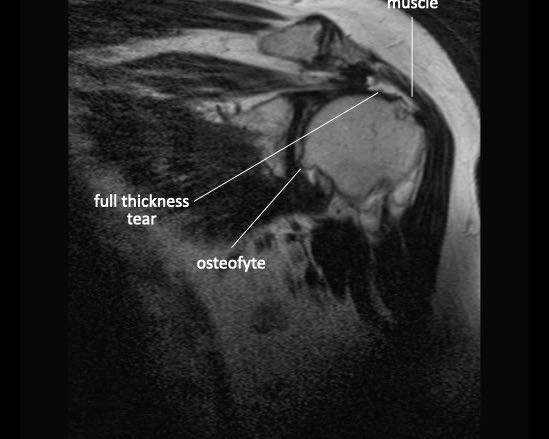

Rách toàn bộ chiều dày

Rách toàn bộ chiều dày (Full Thickness Tear – FTT) là tổn thương kéo dài từ mặt túi hoạt dịch (bursal surface) xuyên suốt đến mặt khớp (articular surface).

Rách toàn bộ chiều dày được phân loại thành:

- FTT không hoàn toàn (Incomplete FTT)

Có rách toàn bộ chiều dày nhưng chỉ một phần chiều rộng của gân bị tổn thương. - FTT hoàn toàn (Complete FTT)

Rách toàn bộ chiều dày được gọi là hoàn toàn khi toàn bộ gân bị đứt. - FTT hoàn toàn + co rút (Complete FTT + retraction)

FTT có biến chứng co rút cơ. - FTT hoàn toàn + co rút + teo cơ (Complete FTT + retraction + atrophy)

FTT có biến chứng co rút cơ, teo cơ và thâm nhiễm mỡ, dẫn đến tiên lượng xấu.

Rách toàn bộ chiều dày hoàn toàn

Nhấp vào hình ảnh để phóng to, sau đó cuộn qua các lát cắt.

Có hình ảnh rách toàn bộ chiều dày gân cơ trên gai kèm co rút và teo cơ.

Lưu ý các dải mỡ trong cơ tròn bé, cơ trên gai và cơ dưới gai.